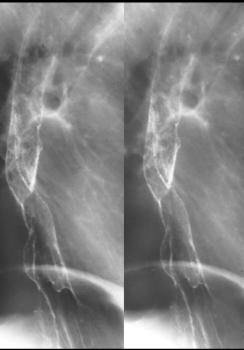

Aspect TOGD en double

de contrast de carcinome epidermoide : Forme

polypoide : lesion en surrelevee nodulaire

endoluminle sans infiltration prietale |

Forme ulceree :

Faible de rigidite parietale et expantion reguliere

locale de la lumiere |